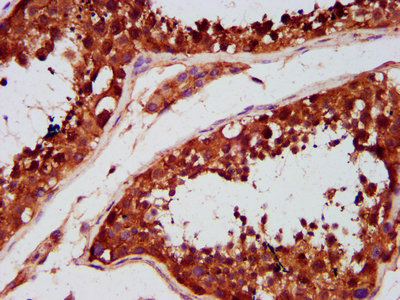

IHC image of CSB-PA803114LA01HU diluted at 1:500 and staining in paraffin-embedded human testis tissue performed on a Leica BondTM system. After dewaxing and hydration, antigen retrieval was mediated by high pressure in a citrate buffer (pH 6.0). Section was blocked with 10% normal goat serum 30min at RT. Then primary antibody (1% BSA) was incubated at 4°C overnight. The primary is detected by a biotinylated secondary antibody and visualized using an HRP conjugated SP system.